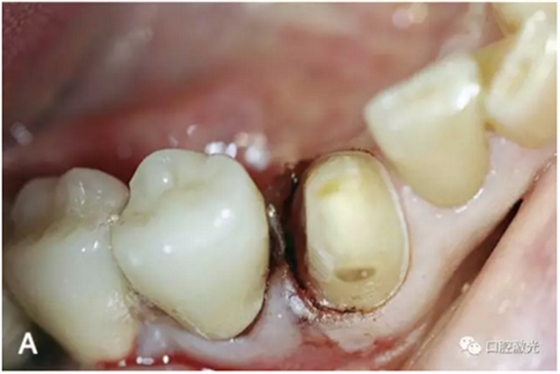

激光在牙冠延長(zhǎng)術(shù)中的應(yīng)用

隨著美學(xué)修復(fù)和保存修復(fù)的不斷發(fā)展,牙冠延長(zhǎng)術(shù)在臨床中的應(yīng)用越來(lái)越多。牙冠延長(zhǎng)術(shù)的目的是在符合牙周生物學(xué)寬度條件下暴露更多的健康牙體組織。